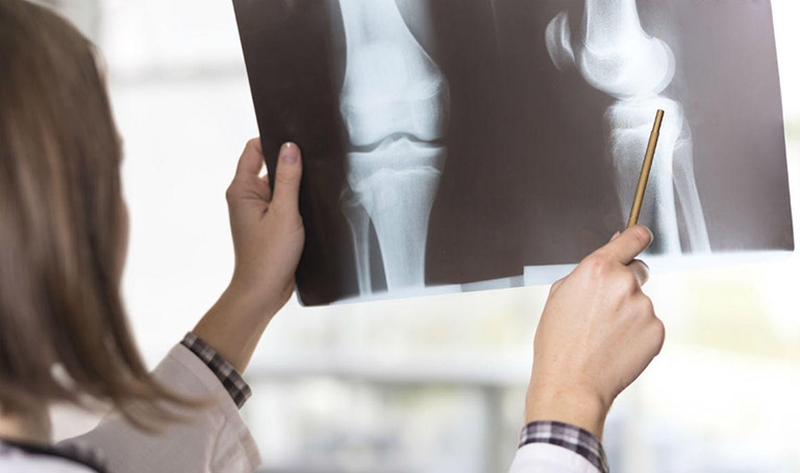

Sau khi thăm khám, chụp X - quang và các xét nghiệm khác, bác sĩ sẽ chỉ định phương pháp điều trị phù hợp:

- Điều trị bảo tồn gãy xương bánh chè không di lệch (2 mảnh và lồi mặt khớp xương bánh chè, lồi cầu đùi không cong) hoặc áp dụng cho bệnh nhân cao tuổi không thể đi lại hoặc gặp các vấn đề nghiêm trọng về sức khỏe.

- Phẫu thuật được chỉ định cho gãy xương , 2 mảnh gãy cách nhau trên 4mm, gãy khi bề mặt khớp của các mảnh gãy bị xoắn lại hoặc có mảnh di chuyển trong khớp gối. Có thể tiến hành mổ khớp để buộc dây thép, mổ buộc xương chữ U, phẫu thuật bằng vít hay mổ với neo chịu lực. Nếu gãy quá nặng, xương bánh chè phải được phẫu thuật cắt bỏ.